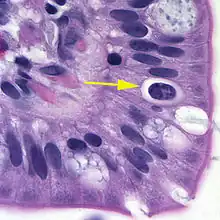

Oocyst in epithelial cyst of mammalian host

The coccidian parasite Cystoisospora belli infects the epithelial cells of the small intestine, and is the least common of the three intestinal coccidia that infect humans (Toxoplasma, Cryptosporidium, and Cystoisospora).

At time of excretion, the immature oocyst contains usually one sporoblast (more rarely two). In further maturation after excretion, the sporoblast divides in two, so the oocyst now contains two sporoblasts. The sporoblasts secrete a cyst wall, thus becoming sporocysts; and the sporocysts divide twice to produce four sporozoites each. Infection occurs by ingestion of sporocyst-containing oocysts: the sporocysts excyst in the small intestine and release their sporozoites, which invade the epithelial cells and initiate schizogony. Upon rupture of the schizonts, the merozoites are released, invade new epithelial cells, and continue the cycle of asexual multiplication. Trophozoites develop into schizonts which contain multiple merozoites. After a minimum of one week, the sexual stage begins with the development of male and female gametocytes. Fertilization results in the development of oocysts that are excreted in the stool. Cystoisospora belli infects both humans and animals.

Microscopic demonstration of the large typically shaped oocysts is the basis for diagnosis. Because the oocysts may be passed in small amounts and intermittently, repeated stool examinations and concentration procedures are recommended. If stool examinations are negative, examination of duodenal specimens by biopsy or string test (Enterotest) may be needed. The oocysts can be visualized on wet mounts by microscopy with bright-field, differential interference contrast (DIC), and epifluorescence. They can also be stained by modified acid-fast stain.